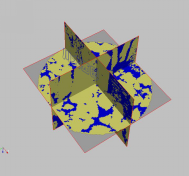

4、三维图像重建及分析

三维重建是指对三维物体建立适合计算机表示和处理的数学模型,是在计算机环境下对其进行处理、操作和分析其性质的基础,也是在计算机中建立表达客观世界的虚拟现实的关键技术。